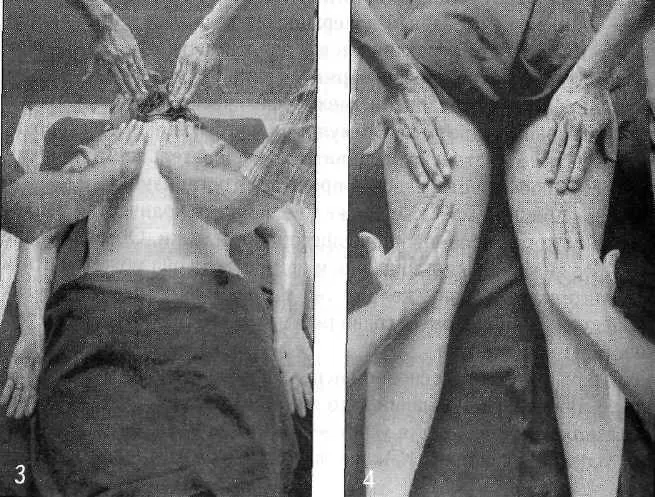

Бахья снехана представляет собой последовательность массажных движений, выполняемых в следующих направлениях: от пупка к голове, от головы к пупку, от пупка к ногам и от ног к пупку — на передней и задней поверхностях тела. Давление, прилагаемое массажистом, различается в зависимости от массируемой области (присутствия точек мармы). Согласно аюрведе, в точках мармы происходит соединение между физической материей тела и его внутренней мудростью. Стимуляция мармы оживляет и координирует взаимодействие субдош ваты, а следовательно, гармонизирует все нейрофизиологические процессы в организме.

Давление при массаже также увеличивает количество теплого кунжутного масла, проникающего в поры кожи. Обычно мы не думаем о коже как о поглощающем органе, хотя она может впитать действительно большое количество масла. Так же как и в других процедурах панчакармы, травяные масла выбираются с учетом конституции пациента.

Массаж и травы позволяют маслу проникать глубоко в ткани и разрыхлять «укладку» амы в этих тканях, в том числе на стенках шрот. Помимо этого, снехана увеличивает гибкость тела, увеличивает силу, уменьшает стресс и питает ткани. Слово «снехана» буквально означает «доброта, нежность, любовь», и эта приятная процедура оправдывает свое название.